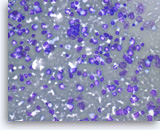

Non-Hodgkin B-cell lymphoma,

Pancreas FNA, Direct Smear.

The aspirates show dispersed single intermediate to large atypical lymphocytes.

20X

Non-Hodgkin B-cell lymphoma,

Pancreas FNA, Direct Smear.

The aspirates show dispersed single intermediate to large atypical lymphocytes.

20X

Non-Hodgkin B-cell lymphoma,

Pancreas FNA, Direct Smear.

At a higher magnification, the atypical lymphocytes show variations in size and shape. Scattered lymphoglandular bodies are seen in the background.

40X

Non-Hodgkin B-cell lymphoma,

Pancreas FNA, Direct Smear.

At a higher magnification, the atypical lymphocytes show variations in size and shape. Scattered lymphoglandular bodies are seen in the background.

40X

Non-Hodgkin B-cell lymphoma,

Pancreas FNA, Cell Block.

Atypical lymphoid infiltrates are present in fibrotic tissue fragment. The atypical cells are intermediate to large in size and have irregular nuclear contours and conspicuous nucleoli. Flow cytometry of the aspirates demonstrates a monoclonal B-cell lymphoma. Overall, the findings are consistent with diffuse large B-cell lymphoma.

40X

Non-Hodgkin B-cell lymphoma,

Pancreas FNA, Cell Block.

Atypical lymphoid infiltrates are present in fibrotic tissue fragment. The atypical cells are intermediate to large in size and have irregular nuclear contours and conspicuous nucleoli. Flow cytometry of the aspirates demonstrates a monoclonal B-cell lymphoma. Overall, the findings are consistent with diffuse large B-cell lymphoma.

40X